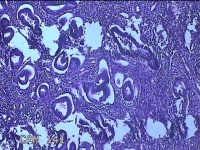

宫腔内容物

性别

女

年龄

43岁

临床诊断

异常子宫出血

一般病史

月经不规则2年余,发现宫颈赘生近1年,宫颈外科可见多个赘生物。

标本名称

大体所见

纱布一块,内有灰白暗红色不规则碎组织1.8x1.3x0.3cm一堆。